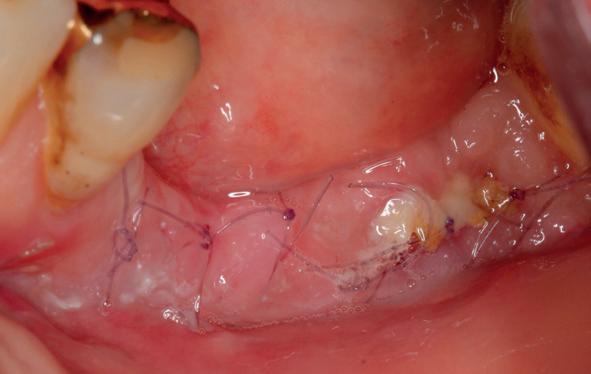

• Aanvulling zachte weefsels met de VISTA techniek en een vrij gingivatransplantaat uit het palatum links en direct dragen van de essix retainer

pincisies met hechtingen naar het buccale en coronale deel getrokken en aldaar ingehecht. Met twee incisies werd ook de emergence profile gecreëerd (afbeelding 6-13). Voor een goede genezing van het

11. Middels hechtingen het op de juiste plek trekken van het transplantaat

12. Transplantaat ingehecht

13. Occlusaal beeld verdikking van de zachte weefsels

14. Direct postoperatief plaatsen

van de essix met 2 dummy tanden

15. Twee weken post operatief